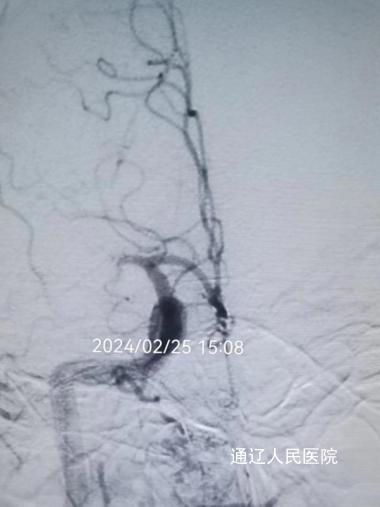

年纪这么小,为什么会出现偏瘫?卒中中心值班医师刘美玉心中充满了疑问,经过详细地询问病史及体格检查,结合头颅CT结果,并与上级医师沟通后,刘美玉医师给出了初步诊断——急性缺血性脑血管病。医师与家属充分沟通并取得其同意后,立刻给予静脉溶栓治疗,为患者争取血管再通的机会。因患者神经功能缺损较严重,介入组医师会诊后,做进一步脑血管造影检查,结果提示患者右侧大脑中动脉闭塞,为责任血管。西院神经外科张永哲主任,神经内一科张建辉主任为其进行脑动脉溶栓、动脉取栓、球囊扩张及支架置入术,手术历时3个小时,过程虽波折,但结局很好,实现了闭塞动脉的再通。

术前